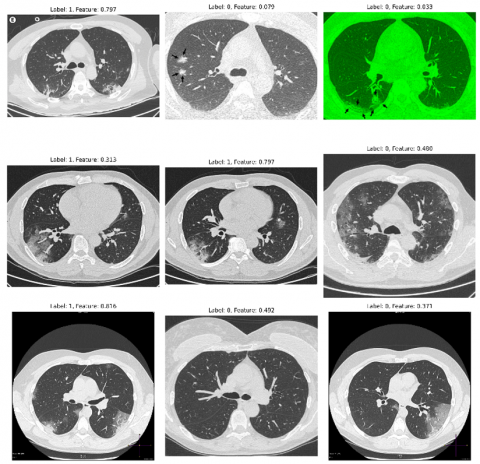

Overall, these metrics suggest that the model has high accuracy in diagnosing COVID-19 from chest CT scan images, with a relatively low rate of false positives (patients incorrectly diagnosed with COVID-19) and a very high rate of true positives (COVID-19 patients correctly diagnosed). To visualize our model's predictions, we have used the technique explained by algorithm 3 and is shown in Figure 7.

Figure 7. Grad-CAM visualizations for the predictions

The GradCAM display facilitates the identification of the most crucial areas in a CT scan towards prediction by the model. By visualizing these regions, we can gain insights into what features of the CT scan are most indicative of COVID-19, and potentially use this information to refine your model or develop new diagnostic tools. To further elucidate the capabilities of our GradCAM visualizations, we intend to integrate a detailed analysis of specific instances where our model precisely highlights the CT scan features characteristic of COVID-19.

Figure 7 demonstrates the model's focus, denoted by warmer colours, on regions known to be affected by the virus, such as areas showing ground-glass opacities and pulmonary consolidation. These visual cues are crucial for clinicians as they offer a non-intrusive means to understand the AI's reasoning, thereby making the model's predictions more transparent and trustworthy. By meticulously correlating the highlighted regions with actual symptoms and anomalies associated with COVID-19, we not only verify the model's diagnostic accuracy but also underline its potential as an assistive tool for medical professionals. This endeavour will bridge the current divide between automated diagnostic systems and their real-world clinical application, ensuring that our FL model is not just a black box but a supporter in healthcare decision-making.